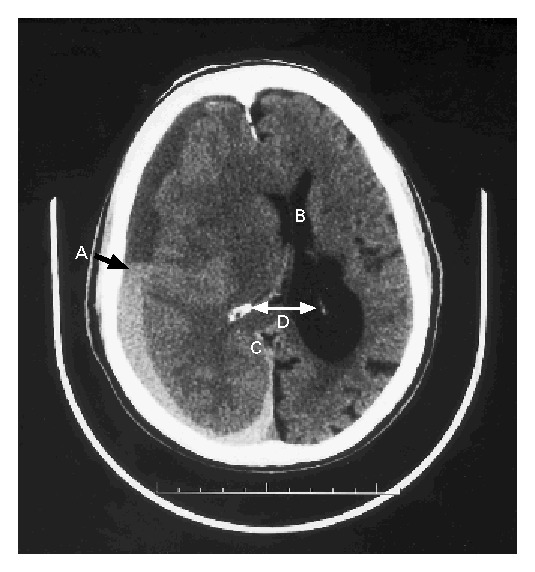

Медицинские аспекты и диагностика субдуральной гигромы мозга